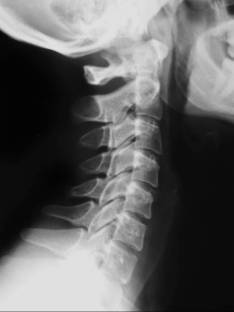

Se realiza un breve interrogatorio. Un examen físico para evaluar la región del dolor, la movilidad, la fuerza, la sensibilidad y se realizan radiografías cervicales y de ser necesario una resonancia magnética nuclear (RMN).

- estructura ósea (fractura, luxaciones, artrosis),

- estructura neurológica (médula espinal, nervios cervicales),

- estructura discal (protusiones, hernias discales),

- postura cervical (rectificación, inversión).